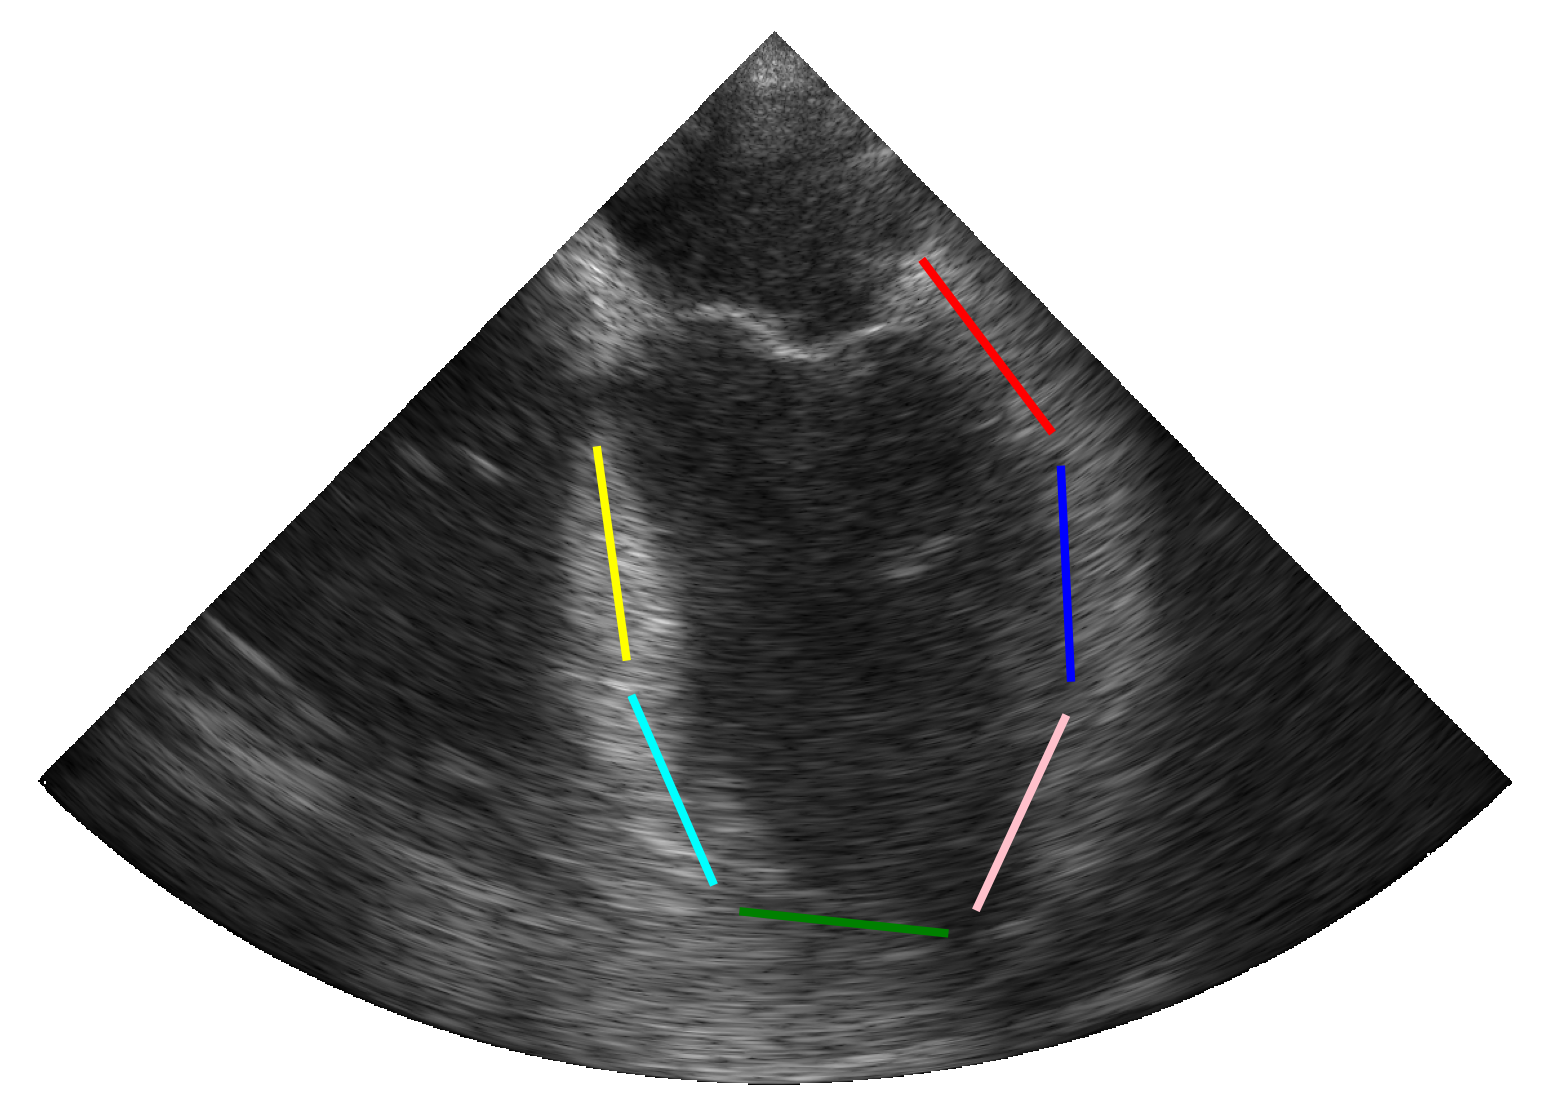

(a)

(b)

(c)

(d)

2.3.2 Simulation of Synthetic Infarction

To account for patients with hypokinetic pathologies, we enhanced the simulation pipeline by designing additional scenarios that simulate myocardial infarction in one of the six cardiac segments. Based on the pipeline described above (c.f. Figure 1), a synthetic myocardial motion was first estimated from a real sequence using the same technique as previously described [14]. The longitudinal contraction of myocardial scatterers was then reduced locally (i.e. at the center of a specific segment) following a Gaussian distribution throughout the cardiac cycle. The scatterers in the surrounding tissues were finally designed to compensate for the reduced contractility in order to maintain overall contraction, thus enabling the rest of the pipeline to be preserved.